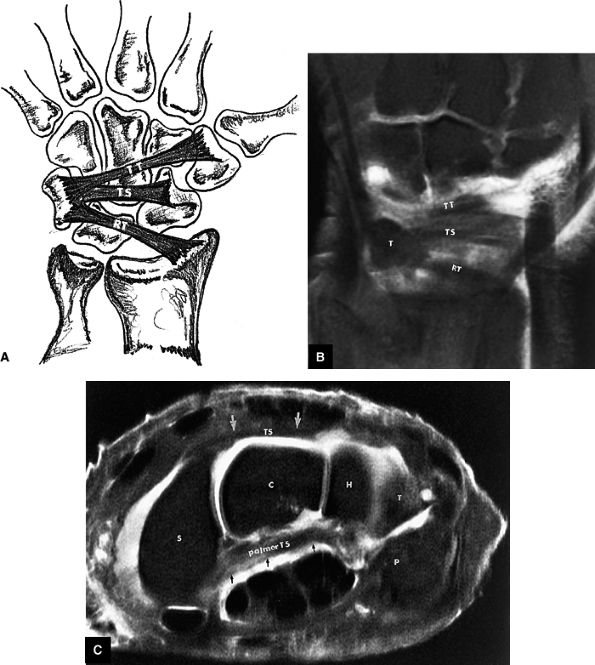

FIGURE 10.71 ● Patterns of the dorsal carpal ligaments. (A) Illustration and (B) corresponding FS T1-weighted coronal image of a single radiotriquetral ligament (RT) and the triquetroscaphoid (TS) and triquetrotrapezial (TT) fascicles of the dorsal intercarpal ligament. T, triquetrum. (C) On an FS PD FSE axial image, the TS fascicle is seen dorsally between the triquetral bone and dorsal pole of the scaphoid (S). The TS fascicle (arrows) extends over the hamate (H) and capitate (C). The palmar TS ligament is also identified at this level (arrows). P, pisiform.